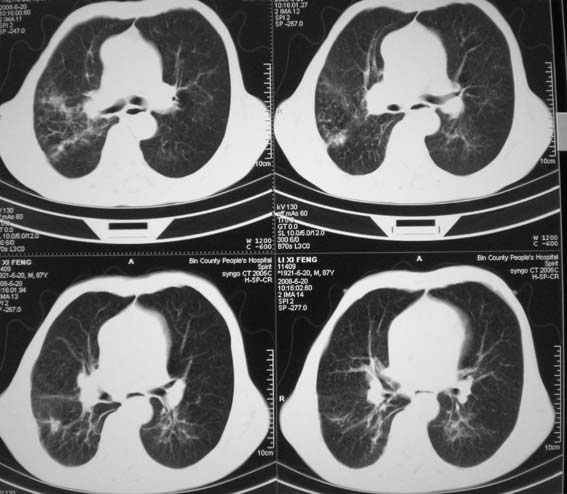

标题: CT12538:男,87岁,请会诊!

男,87岁,咳嗽、发烧、有黄痰,胸片示肺结核。

右肺上叶尖后段片状不规则致密影,密度欠均匀,相邻胸膜肥厚,纵隔内见多发肿大、钙化淋巴结,考虑为结核,部分坏死

有低密度坏死灶;结合痰检。